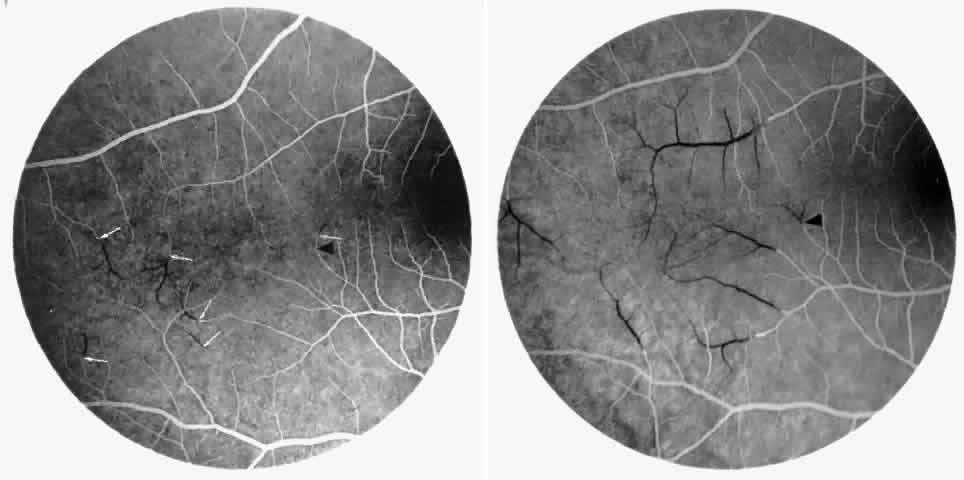

Macular Small Vessel Occlusions

Occlusions of the fine vasculature of the macular and perimacular area have been reported in 10% to 40% of patients with sickle cell disease.18,83,91–99 In the acute phase, the occluded vessel will have a dark red appearance and may appear as a dark line on fluorescein angiography (Fig. 9). Nerve fiber layer infarcts (cotton-wool spots) are seen (see Fig. 8D and E;Fig. 10).100

Fig. 9. A 27-year-old man with homozygous sickle cell anemia. A. Fluorescein angiogram of the right eye shows multiple arteriolar occlusions temporal to the fovea (arrows). B. Same area 6 months later shows more extensive occlusions. The black arrowheads (A and B) identify corresponding arteriolar bifurcation.

Fig. 10. A 33-year-old woman with SC disease and stage III sickle cell retinopathy. A. Photograph of the right eye shows a cotton-wool spot with a dark segment identifying the occluded vessel (arrow). B. Fluorescein angiogram demonstrates nonfilling of the occluded vessel (arrow). C. Eighteen months later, the occluded vessel is still visible (arrow). D. Fluorescein angiogram demonstrates that there is still nonfilling of the vessel (arrow).

Other macular and perimacular changes include microaneurysm-like dots, dark and enlarged segments of arterioles, hairpin-shaped venular loops, pathologic avascular zones, and widening and irregularities of the foveal avascular zone (Figs. 11 and 12). In the Jamaican cohort study evaluating children with homozygous sickle cell anemia and SC disease between the ages of 5.0 and 7.5 years of age, no pathologic avascular zones could be identified despite a high incidence of peripheral vascular closure.31 In evaluating patients with homozygous sickle cell anemia, no relationship between ISC counts and macular abnormalities or visual acuity could be found.101 Using fluorescein angiography, investigators have found the foveal avascular zone to be significantly larger in eyes with clinical evidence of sickle cell maculopathy as compared with normal eyes and eyes without clinical evidence of sickle cell maculopathy.102–104

Fig. 11. A. A 40-year-old woman with homozygous sickle cell anemia. A fluorescein angiogram demonstrates multiple microaneurysm-like dots with fluorescein leakage, hairpin loop (arrowhead), pathologic avascular zones (arrows), and a widened, irregular foveal avascular zone (FAZ). B. Fluorescein angiogram of a 30-year-old woman with homozygous sickle cell anemia demonstrates multiple microaneurysm-like dots and a widened, irregular FAZ.

Fig. 12. A. Fluorescein angiogram of the left eye of a 40-year-old man with homozygous sickle cell anemia, demonstrating an irregular foveal avascular zone (FAZ), hairpin loops, and loss of the temporal capillary network. B. Fluorescein angiogram of the right macula of a 38-year-old woman with homozygous sickle cell anemia, showing an abnormal FAZ, hairpin loop (arrowhead), and pathologic avascular zones (arrows).

Careful examination by fluorescein angiography, looking for areas of capillary dropout and other capillary abnormalities, is often necessary to identify the macular changes. These changes may be transient, and the macula may appear normal on subsequent fluorescein angiograms (Fig. 13). Although fluorescein angiography may or may not demonstrate reperfusion of a previously occluded capillary bed, a loss of the inner retinal layers results in an ophthalmoscopic focal concavity with an abnormal reflex (retinal depression sign) (see Fig. 8E).105,106 These changes are usually permanent. The retinal depression sign is not pathognomonic of sickle cell disease and may be seen with other arteriolar occlusive diseases, such as embolic retinopathy, vasculitis, and hypertension.

Fig. 13. A. A 32-year-old man with homozygous sickle cell anemia and proliferative sickle retinopathy. A fluorescein angiogram shows temporal occlusions and a pathologic avascular zone (PAZ) temporal to the foveal avascular zone. B. Seven years later, there is filling of the previously noted PAZ.